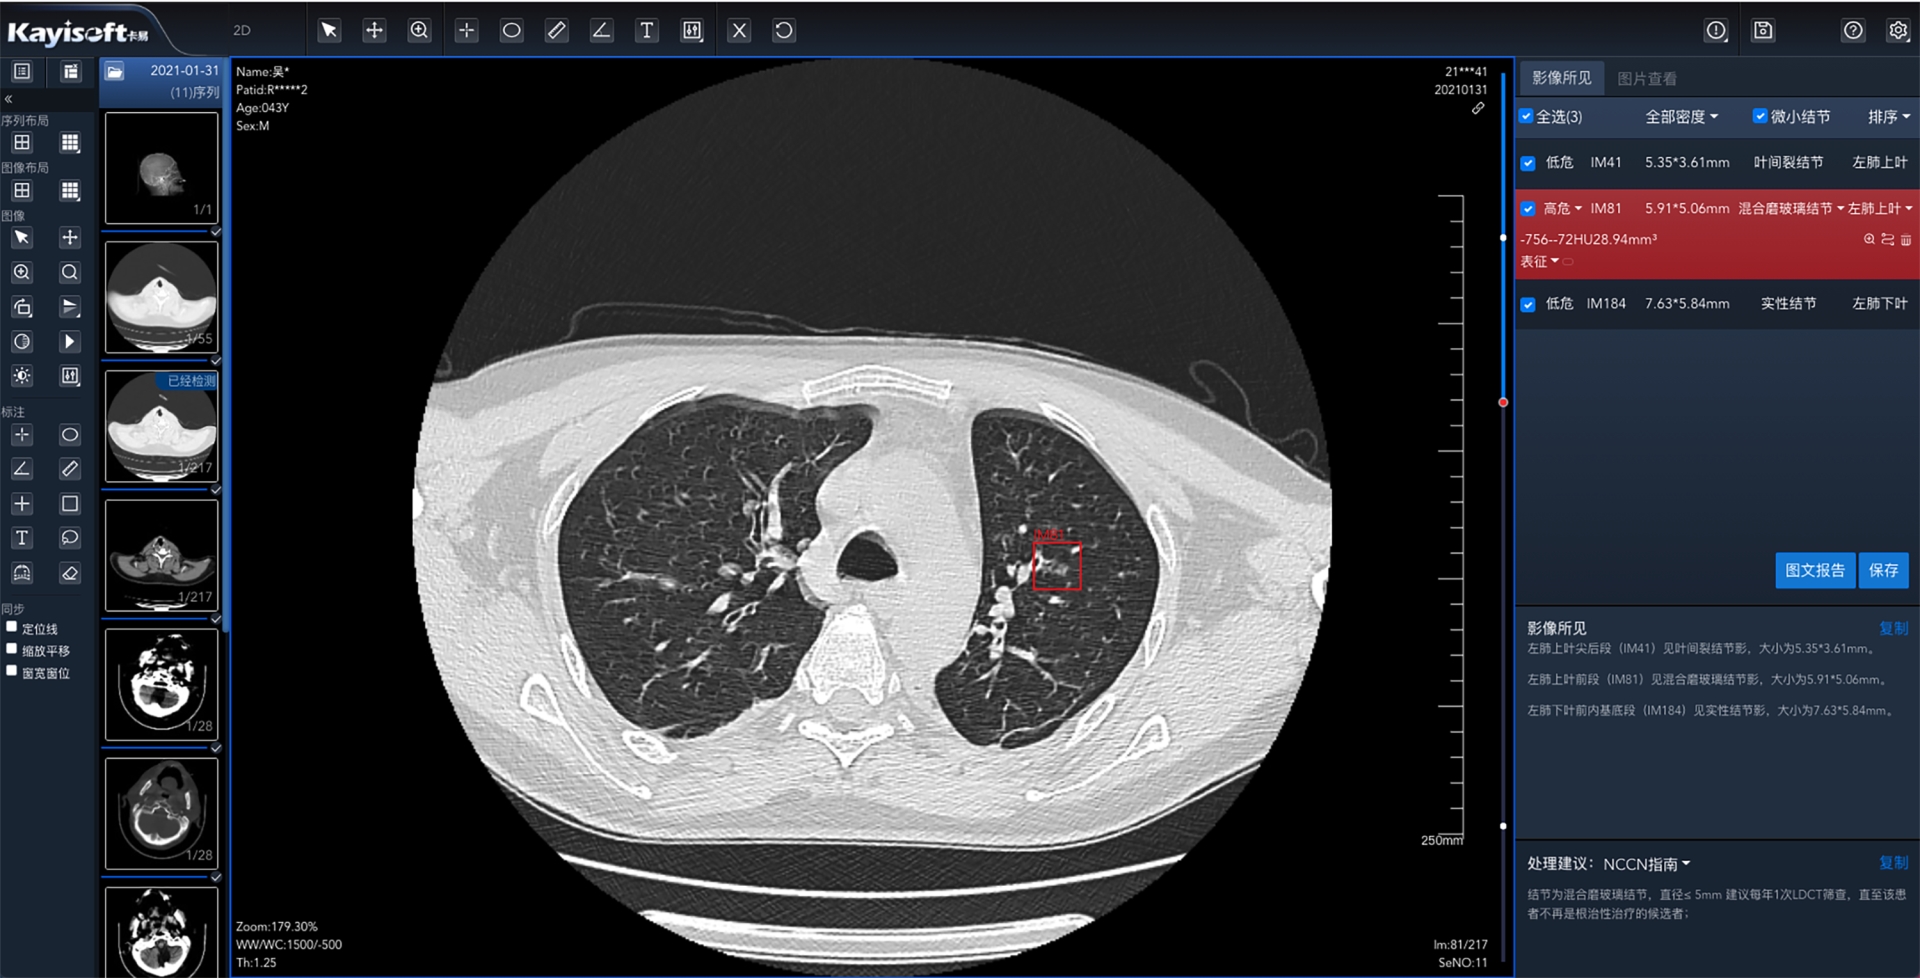

基于全市区域影像云肺结节AI分析服务是通过温州市医学影像云平台完成区域医疗影像数据云化管理数据统一采集,实现以数据为基础,结合AI分析服务肺结节智能标注,在短时间内分析完成并生成“AI结构化报告”和“指南参考”来协助诊断医生参考,提高工作效率。

AI分析服务+影像云的优势组合,能够统筹服务器资源,统一维护便于管理;资源分配更加均匀,使得基层医院也能具备大型三甲医院的诊断能力;各医院可通过基于影像云肺结节AI分析服务实时调阅影像,针对温州市范围内的肺结节病例进行量化指标的统计分析。

本产品在辅助医师临床诊断、体检筛查、辅助科研等诸多领域都有着相当大的应用价值和发展前景,有利于区域管理手段现代化,为未来AI的动态跟踪和大数据分析提供强有力的基础支撑。